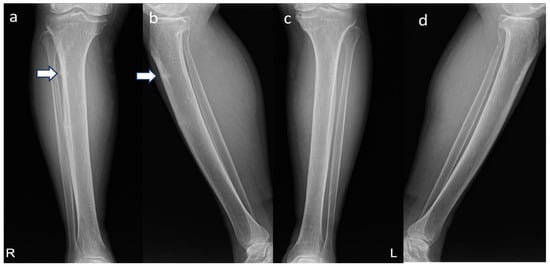

2. Case Presentation